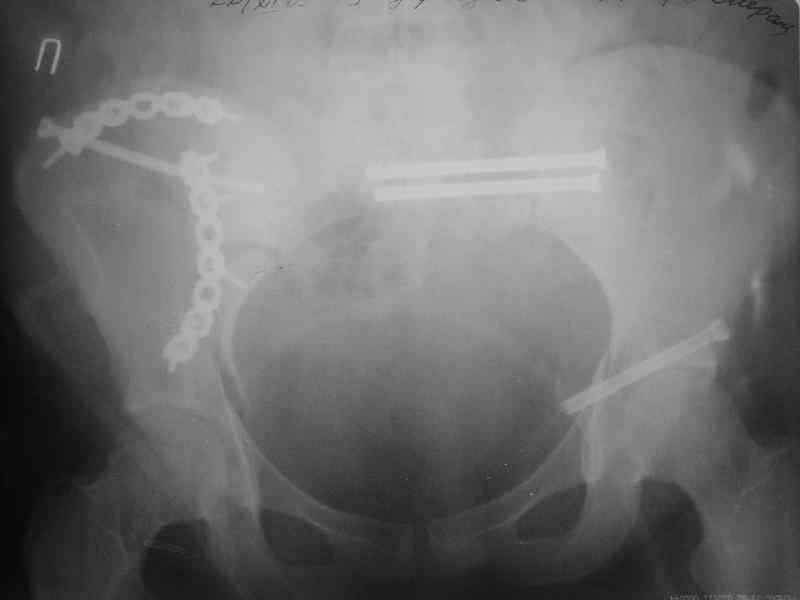

Молодая девушка 19 лет, травма 1 год назад, тогда же прооперирована.

В настоящее время имеются ноющие боли в области крестца слева, нарушение походки, ощущение неуверенности, слабости в левой нижней конечности, неврологически -непостоянные парестезии в левой нижней конечности. Ходит с дополнительной опорой, страдает от ожирения.

В приложении снимки при поступлении и послеоперационные год назад.

Могу сказать одно: миграция винтов и нестабильность синтеза левого подвздошно-крестцовогоо сочленения очевидна.